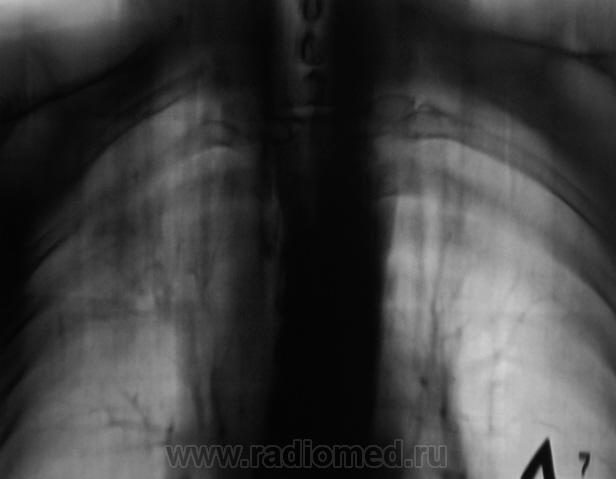

И откуда он берется? Очередной контроль после флюорографии.

Контроль передвижного флюорографа.

Сегодня дообследовали.

да тубркулеза у Вас хватает!

Не оказался "пневмонией". Сегодня пришел коллега фтизиатр записать изображения на диск, посылает пациента в ОПТД, палки найдены.